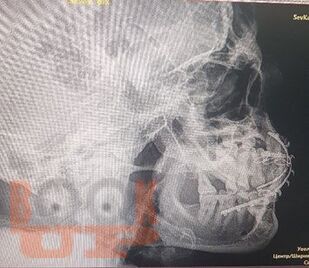

В учебном пособии представлены основные методы дополнительного исследования в челюстно-лицевой хирургии в соответствии с действующим учебным планом и программой обучения студентов-стоматологов.

Дополнительные методы исследования в челюстно-лицевой хирургии представлены лучевыми, ультразвуковыми методами диагностики, а также специальными методиками, позволяющими детализировать патологию зубочелюстной системы пациента с целью постановки окончательного диагноза и составления плана лечения.